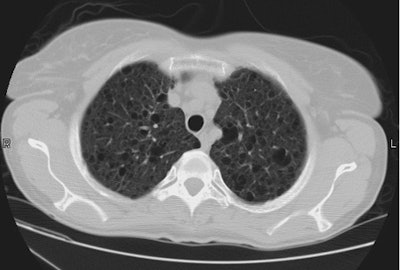

Esophageal carcinoma: The patient shown below presented with a history of progressive dysphagia. A barium swallow revealed a distal esophageal mass. CT and FDG PET imaging were performed for patient staging. The large esophageal mass (white arrows on CT) demonstrated intense tracer uptake (black arrows on PET scan). Uptake could also be seen in regional gastrohepatic ligament nodal metastases (right images). Retrocrural metastases seen on CT blended imperceptibly with the primary tumor on PET imaging. The was no evidence of distant metastatic disease. (Click here to view rotating volume image [1.5 MB])